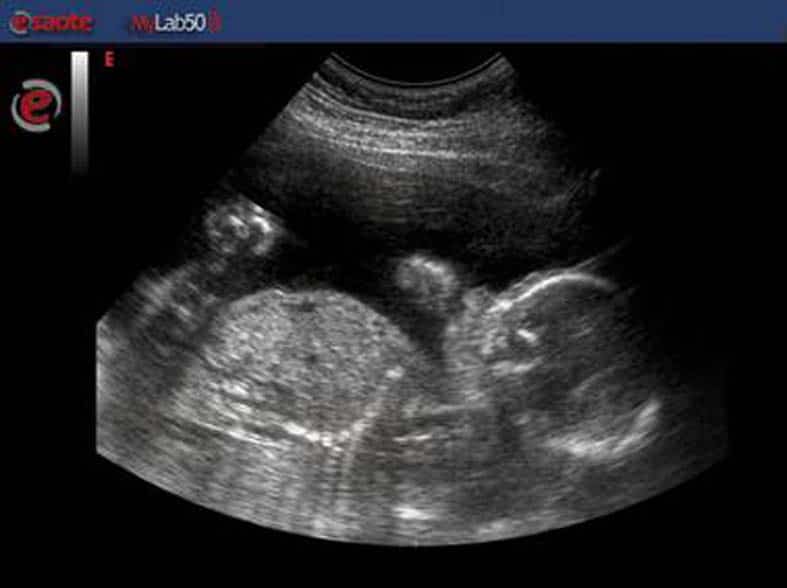

Si chiama Esaote mylab 50 gold. E' in dotazione al distretto socio sanitario del Casentino per le visite ostetriche e ginecologiche

Il distretto socio-sanitario di Bibbiena ha in dotazione un ecografo di ultima generazione per le visite ostetriche e ginecologiche. Si chiama Esaote mylab 50 gold ed è entrato in funzione da qualche giorno. Finora è stato utilizzato solo dal medico, ma a breve potranno servirsene anche le ostetriche dopo un corso di formazione di 20 ore completato a dicembre e una specifica autorizzazione.

Questo ecografo permette numerose operazioni: il controllo del primo trimestre di gravidanza, sapere il numero degli embrioni, il battito cardiaco embrionale e l’eventuale presenza di  anomalie uterine o annessiali. Con la prima ecografia si può datare la gravidanza in base alla lunghezza cranio-caudale del feto.

Il nuovo ecografo viene usato anche per vedere la posizione della spirale (contraccettivo) e la datazione e visualizzazione della gravidanza in utero per le donne in preospedalizzazione che vogliono interrompere la gravidanza.